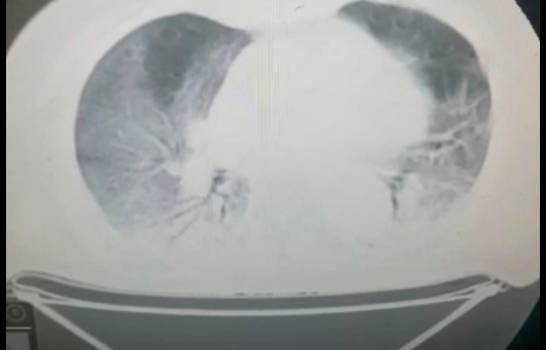

La afirmación la realiza el ministro de Salud Pública, Daniel Rivera, en declaraciones a Diario Libre, al señalar a través de unas radiografías del tórax, que los no vacunados llegan a los centros hospitalarios con los pulmones altamente comprometidos.